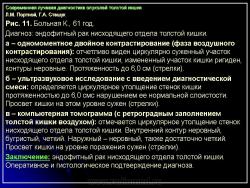

КТ толстой кишки значительно расширила возможности лучевой диагностики заболеваний полых органов желудочнокишечного тракта и в настоящее время стала более широко использоваться, в том числе и при опухолевых поражениях толстой кишки. КТ проводили после обязательного рентгенологического и эндоскопического исследований. На первом этапе серией последовательных срезов исследовали всю брюшную полость до области малого таза включительно. Для контрастирования просвета толстой кишки больному за 12 ч до исследования (после предварительного очищения кишечника) давали пить 5% раствор урографина – 500 мл дробно и 500 мл также дробно за 2 ч до исследования. Сложность и вариабельность формы и положения толстой кишки, изменчивость ее положения по отношению к продольной оси тела не позволяют получить стандартные томограммы, так как различные участки кишки попадают в срез продольно, поперечно или косо. Все это, вместе с различным содержимым в петлях кишки, затрудняет анализ состояния стенок кишки в зоне поражения. Если были сомнения в правильности полученной картины, то проводилось исследование зоны интереса с ретроградным введением воздуха в толстую кишку. Толщина кишечной стенки в норме зависит от степени растяжения кишки, но у здорового человека не превышает 5 мм.

Отображение опухоли толстой кишки на компьютерных томограммах зависит от локализации процесса и характера роста. При преимущественно диффузном внутристеночно растущем раке кишки, что выявлялось гораздо чаще, при КТ отмечалось утолщение стенки кишки с неравномерным, достаточно часто циркулярным сужением просвета соответствующего участка ее, ригидностью стенки (отсутствием изменения диаметра просвета и толщины стенки при дозированном введении воздуха) и неровными внутренними контурами (рис. 11). При экзофитном характере роста опухоли при КТ внутри просвета кишки определялось дополнительное мягкотканное образование с неровными бугристыми контурами, широко прилежащее к стенке кишки. Опухоли были различной структуры: однородной, неоднородной за счет включений кальция или участков распада с наличием в опухолевой ткани жидкости и газа. При появлении газа в околокишечной клетчатке чаще всего предполагалась перфорация ее стенки. Кроме оценки состояния стенок кишки, пораженной опухолью, оцениваются и изменения в окружающих тканях и органах при распространении ее за серозную оболочку. Степень местного распространения опухоли является одним из определяющих факторов прогноза и выбора дальнейшей тактики лечения. Оценку степени распространения опухоли проводили в соответствии с Международной классификацией по системе ТNM.

При КТ слои стенки кишки не визуализируются, в связи с чем разграничить стадии Т1 и Т2 не представляется возможным. Принципиально важно с точки зрения тактики дальнейшего лечения и прогноза заболевания диагностировать прорастание серозной оболочки кишки (Т3) и смежных органов (Т4). Одним из симптомов стадии Т3 является наличие в клетчатке, окружающей кишку, тяжистых или линейных структур, распространяющихся в виде лучей от стенки измененной кишки в жировую ткань или наличия узловой структуры вблизи наружного контура пораженной опухолью стенки кишки (рис. 12).